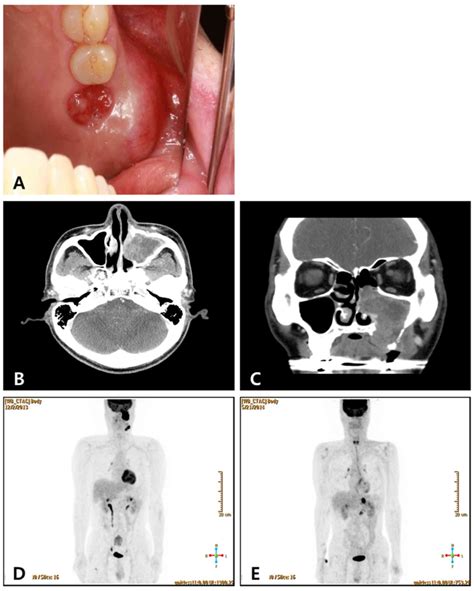

• Oral Cavity (Mucocele): Often appearing on the inner lower lip, tongue, or floor of the mouth.

• A painless, dome-shaped, and often bluish or translucent swelling.

• May fluctuate in size, occasionally bursting and then refilling.

• Can cause minor irritation when eating or speaking if located in a high-friction area.

Understanding the etiology of a Mucous Retention Cyst is key to prevention. In the mouth, the most common culprit is physical trauma. Accidentally biting your lip or cheek can sever the minor salivary gland duct, causing the mucous to spill into the surrounding tissue and form a cyst.

Diagnosing a cyst is usually straightforward. For oral lesions, a dentist or oral surgeon can perform a clinical examination. They look for the characteristic fluid-filled appearance and discuss your history of trauma to the area.